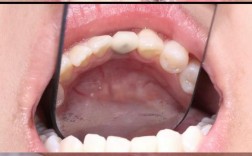

| 临时修复 | 对符合条件的患者,安装临时牙冠,调整咬合避免早接触;无法即刻负重者可缝合牙龈。 | 临时牙冠需降低咬合高度,防止种植体承受过大咬合力。 |